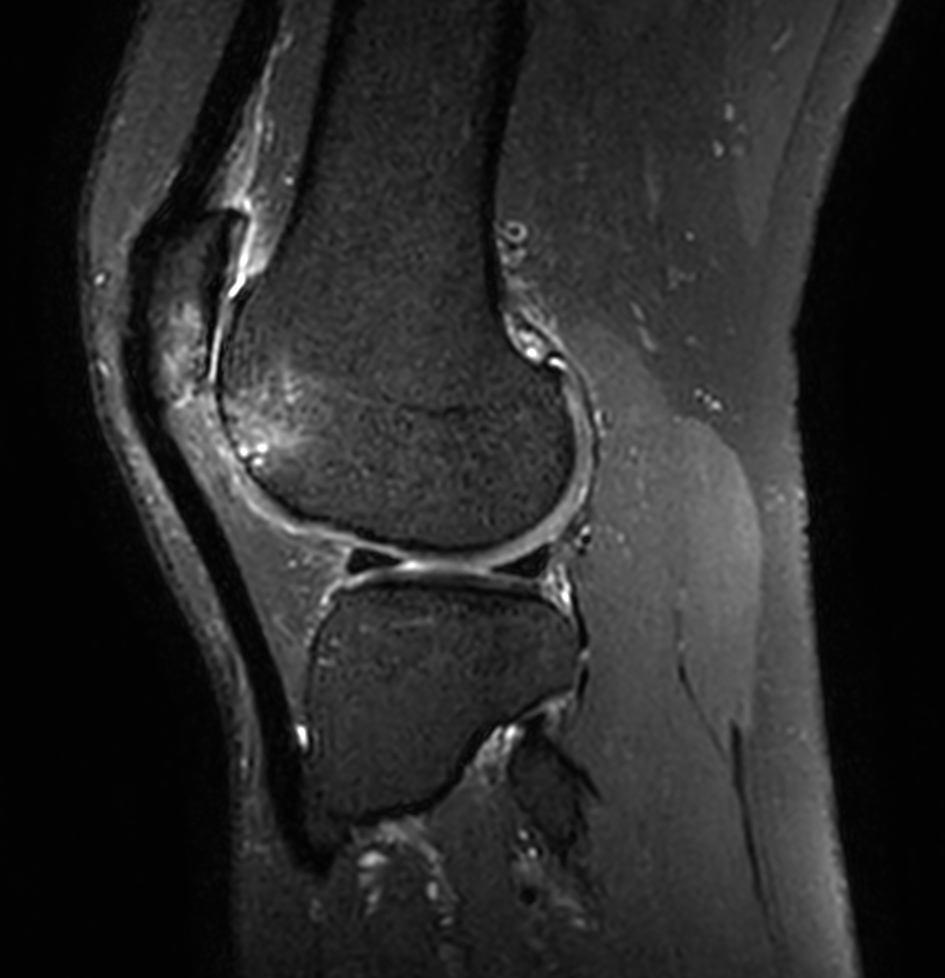

Coronal PDw SPIR